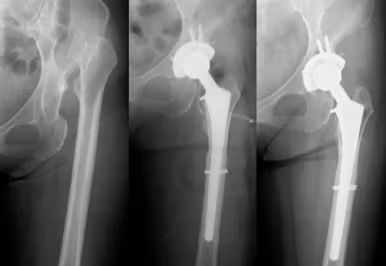

⑤人工股関節周囲骨折

人工股関節置換術後にその周囲の骨折が発生した場合、人工関節の存在から骨折部の固定が困難となります。また、骨折に伴い人工股関節のゆるみが発生した場合は、人工股関節再置換術が必要となります。